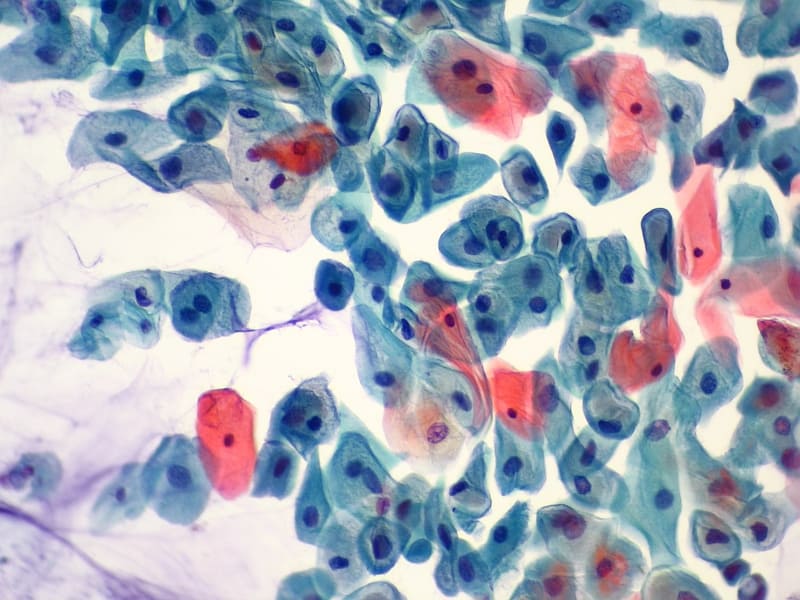

Odebrané buňky jsou natřeny na sklo a zafixovány alkoholovým roztokem. Nedílnou součástí stěru je i dobře vyplněná průvodka k vyšetření, obsahující informace o datu posledního menstruačního krvácení, užívání antikoncepce či délce trvání těhotenství. Fixovaný preparát cytologického stěru je s dokumentací odeslán k vyhodnocení do cytologické laboratoře, kde odborník-cytolog vyšetří a nález se podrobně popíše. K hodnocení je aktuálně v České republice využívána cytologická klasifikace přijatá v USA ve městě Bethesda v roce 2001.

Po velmi podrobném a jednoznačném popisu následuje doporučení dalšího postupu. Cytolog zhodnotí kvalitu stěru, hormonální stav ženy a případnou infekci a zařadí pozorované buňky děložního hrdla do příslušné kategorie.